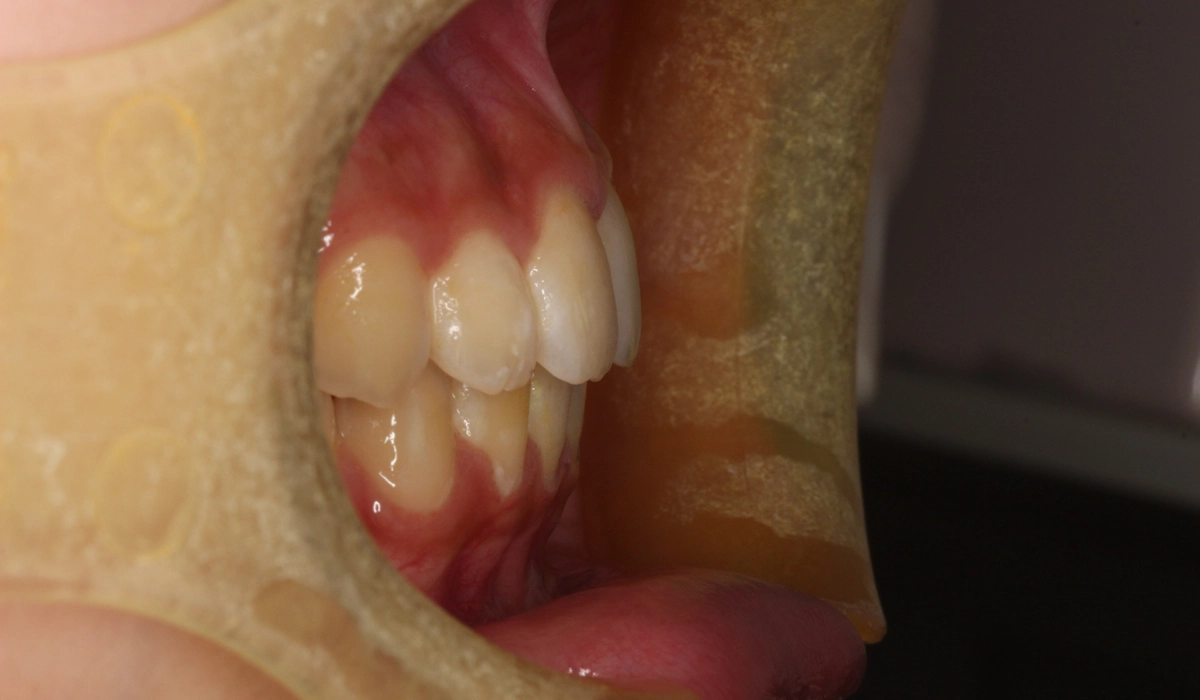

術前:右側

術後:右側